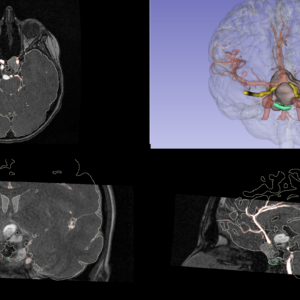

We are pleased to share a new scientific contribution that explores a multidisciplinary and technologically advanced approach to the treatment of pediatric craniopharyngioma—a rare benign tumor of the hypothalamic–pituitary region, often associated with high morbidity. This work stems from the long-standing collaboration between PRINTMED 3D and the “Vittore Buzzi” Children’s Hospital in Milan, and stands as a concrete example of how synergy between clinical practice and research can generate effective, personalized solutions for pediatric neurosurgery.